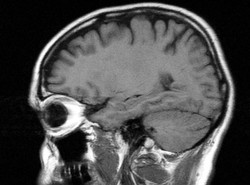

Latanie samolotem miewa nieprzyjemne skutki. Po wielu godzinach spędzonych w ciasnym fotelu i pokonaniu wielu stref czasowych często czujemy się kompletnie rozbici. . Cierpimy na tzw. jet lag - czyli rozregulowanie biologicznego zegara naszego organizmu. Naukowcy wykazali właśnie, że jet lag związany jest z pracą dwóch części pnia mózgu.

Pierwsza, przednia, reaguje na światło wpadające do ludzkiego oka i jest powiązana ze stanem głębokiego snu. Druga, tylna, niezwiązana ze zmianami oświetlenia, odpowiada za sen lekki - tzw. REM. .

Badania przeprowadzone na szczurach wykazały, że gwałtowna zmiana rytmu dnia i nocy powoduje natychmiastowe dostosowanie się pierwszego ośrodka związanego z głębokim snem. Drugi natomiast w ogóle nie reaguje. Aby rytm okołodobowy wrócił z powrotem do normy, .